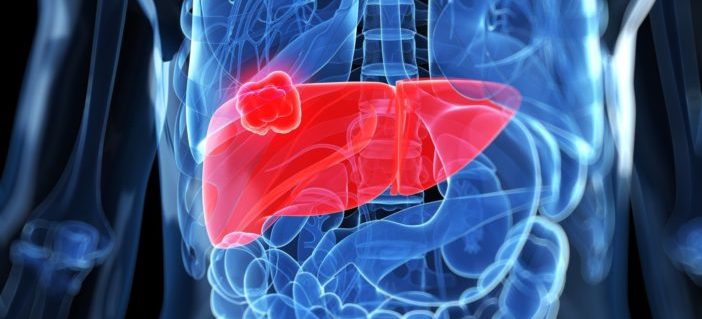

Dr. Lucia Guo (LG): Hepatitis is a disease that happens when the liver, a big organ on the upper right side of the belly, gets inflamed. Hepatitis may be temporary (acute) or long term (chronic) depending on whether it lasts for less than or more than six months.

Hepatitis virus types commonly affect the liver (triangle-like organ on the upper left side of this photo) and make it inflamed.

Chronic hepatitis B develops more commonly in people who are infected with the virus at an early age (often at birth). Most people with chronic hepatitis B have no symptoms until their liver disease is at a late stage. The most common early symptom is feeling tired. Everyone with chronic hepatitis B is at increased risk of developing complications, including liver scarring (called cirrhosis when the scarring is severe) and liver cancer.

The risk of developing complications (such as cirrhosis, liver failure, or liver cancer) depends on how rapidly the virus multiplies and how well your immune system controls the infection.